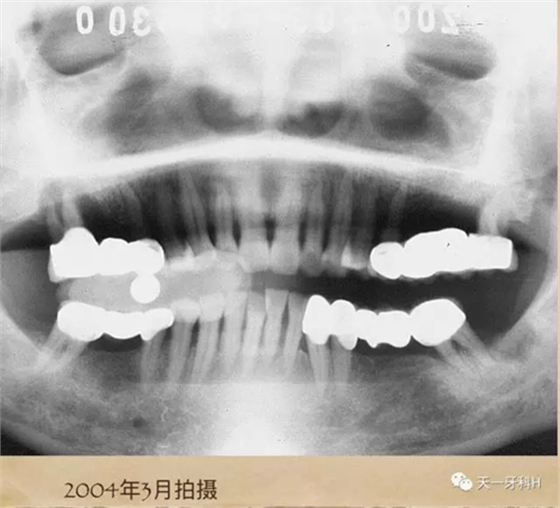

該患者2004年3月16日來本診所就醫(yī),這張曲面斷層片就是當時拍的,患者之前在外院后牙區(qū)全部做了烤瓷連橋,從這張曲面斷層片上看:右上七牙槽骨已經(jīng)破壞到了根尖,右上五也出現(xiàn)了牙周膜間隙增寬,左上后牙的烤瓷橋的基牙也開始出現(xiàn)問題了,我常常講:牙周病患者盡量不要做烤瓷牙,很多患者不理解,我用事實說話:這個牙周病患者就是一個烤瓷牙的受害者,四個后牙區(qū)全部做了烤瓷橋!17已經(jīng)牙槽骨破壞到達了根尖區(qū),15、25、28已經(jīng)開始了牙槽骨破壞,我當時勸她拆除烤瓷橋,她不聽我的話,我只好拍片記錄下來她的現(xiàn)狀,下面就是她當時的牙片: